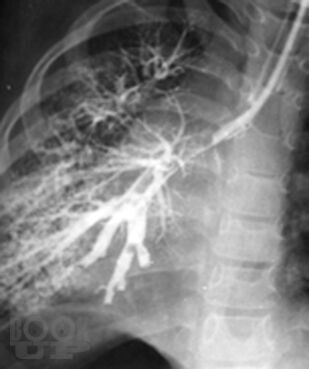

Монография посвящена актуальной проблеме редких (орфанных) заболеваний легких у детей, включающих как собственно наследственные, врожденные, интерстициальные и другие редкие заболевания легких, так и легочные поражения при разнообразной другой редкой патологии. В книге обобщены современные мировые данные, а также многолетний опыт сотрудников клиники пульмонологии Московского НИИ педиатрии и детской хирургии (ныне – НИКИ педиатрии им. акад. Ю.Е. Вельтищева РНИМУ им. Н.И.Пирогова). Для работы над рядом глав привлечены ведущие специалисты из других учреждений страны. Монография адресована детским пульмонологам и аллергологам, практикующим педиатрам и врачам общей практики, другим специалистам, интересущимся орфанной патологией.